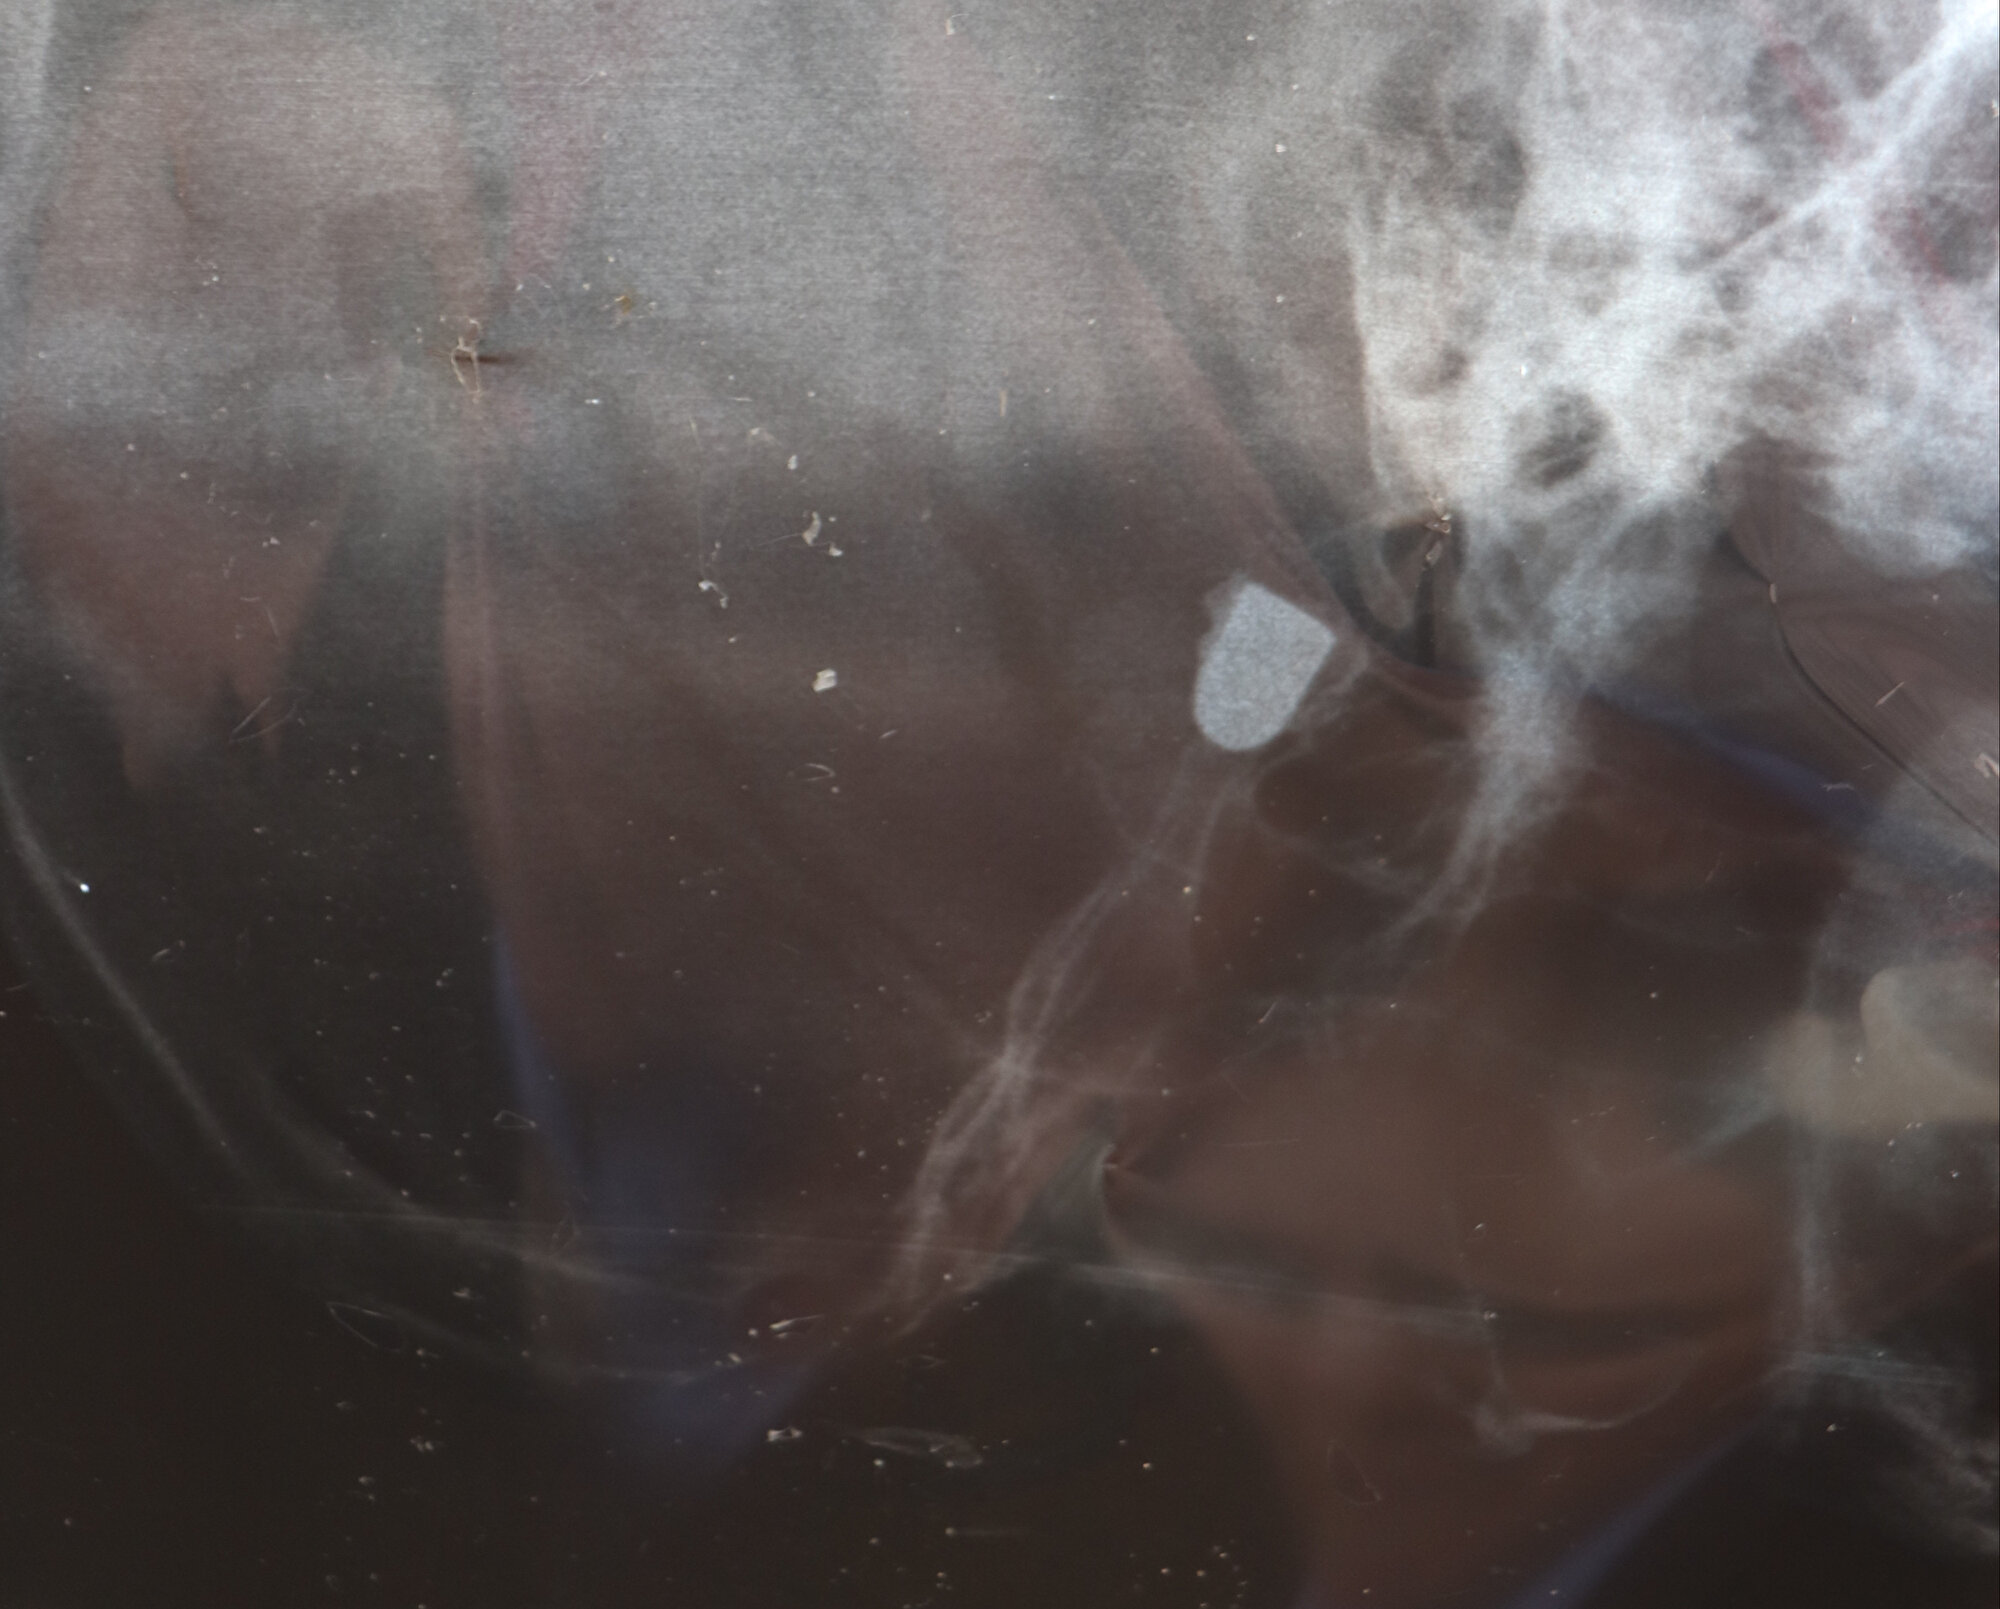

Kafası kanayan Çakmak, ağabeyi ile oynadığı sırada yaralandığını düşünen ailesi tarafından Trabzon'daki bir hastaneye götürüldü. Burada yapılan ilk müdahalenin ardından çekilen röntgen filminde kafasında mermi çekirdeği olduğu tespit edilen Çakmak, Ankara'daki hastaneye sevk edildi.

Kurşunun oluşturduğu tahribat dolayısıyla sol gözü görme yetisini kaybeden, sol kol ve bacağı da felç olan Çakmak, ameliyat edildi. Çakmak'ın kafasındaki mermi çekirdeği, hayati tehlike riski bulunduğu için çıkartılamadı.

Çakmak, kurşunun başının üst kısmından girdiğini ve sol gözünün arka bölümünde kaldığını anlatarak, "45 yıldır geçmeyen baş ağrısı ve uykusuzlukla mücadele ediyorum. Başım ağrıdığı için düzenli ağrı kesici alıyorum. Uyku sorunum var, yattığım zaman sanki biri kafama yumruk atıyormuş gibi acıyla sıçrayıp kalkıyorum. O nedenle de ancak uyku ilacı alarak uyuyabiliyorum" dedi.